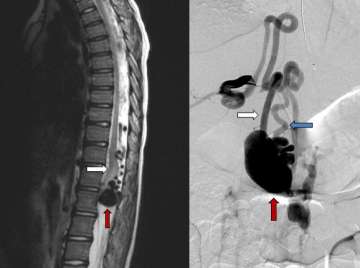

Figure 1. Type I Spinal Dural Arteriovenous Fistula - Spinal angiogram (left image) of a left sided spinal segmental artery (white arrow) with an abnormal connection (red arrow) to a spinal cord vein that has become abnormally enlarged (blue arrow)

• These malformations represent 70% of spinal vascular malformations and are the result of an abnormal connection forming between an artery and a vein in the spinal canal dural covering (Figure 1). This connection allows high pressure arterial blood to escape into the low-pressure network of spinal cord veins. Over time, the spinal cord is damaged by the elevated pressure in the veins. Spinal dural arteriovenous fistulas (AVFs) are thought to form spontaneously during adulthood and are not congenital or hereditary. These lesions rarely rupture or bleed, but they do cause significant spinal cord dysfunction that can result in leg weakness, lower body numbness, imbalance, and urinary problems. These malformations are good candidates for surgical treatment and endovascular treatment, which are typically curative.

Figure 2. Type IV Pial Spinal Arteriovenous Fistula – sagittal or side view of a T2 MRI of the spine (left) showing a massively enlarged spinal vein (red arrow) compressing the spinal cord (white arrow).

• Pial spinal AFVs are a direct connection between an artery and a vein on the surface of the spinal cord. These lesions are very rare and come to attention for various reasons, such as when the vein has become enlarged due to high pressure from the artery and this structure begins to compress the spinal cord (Figure 2).